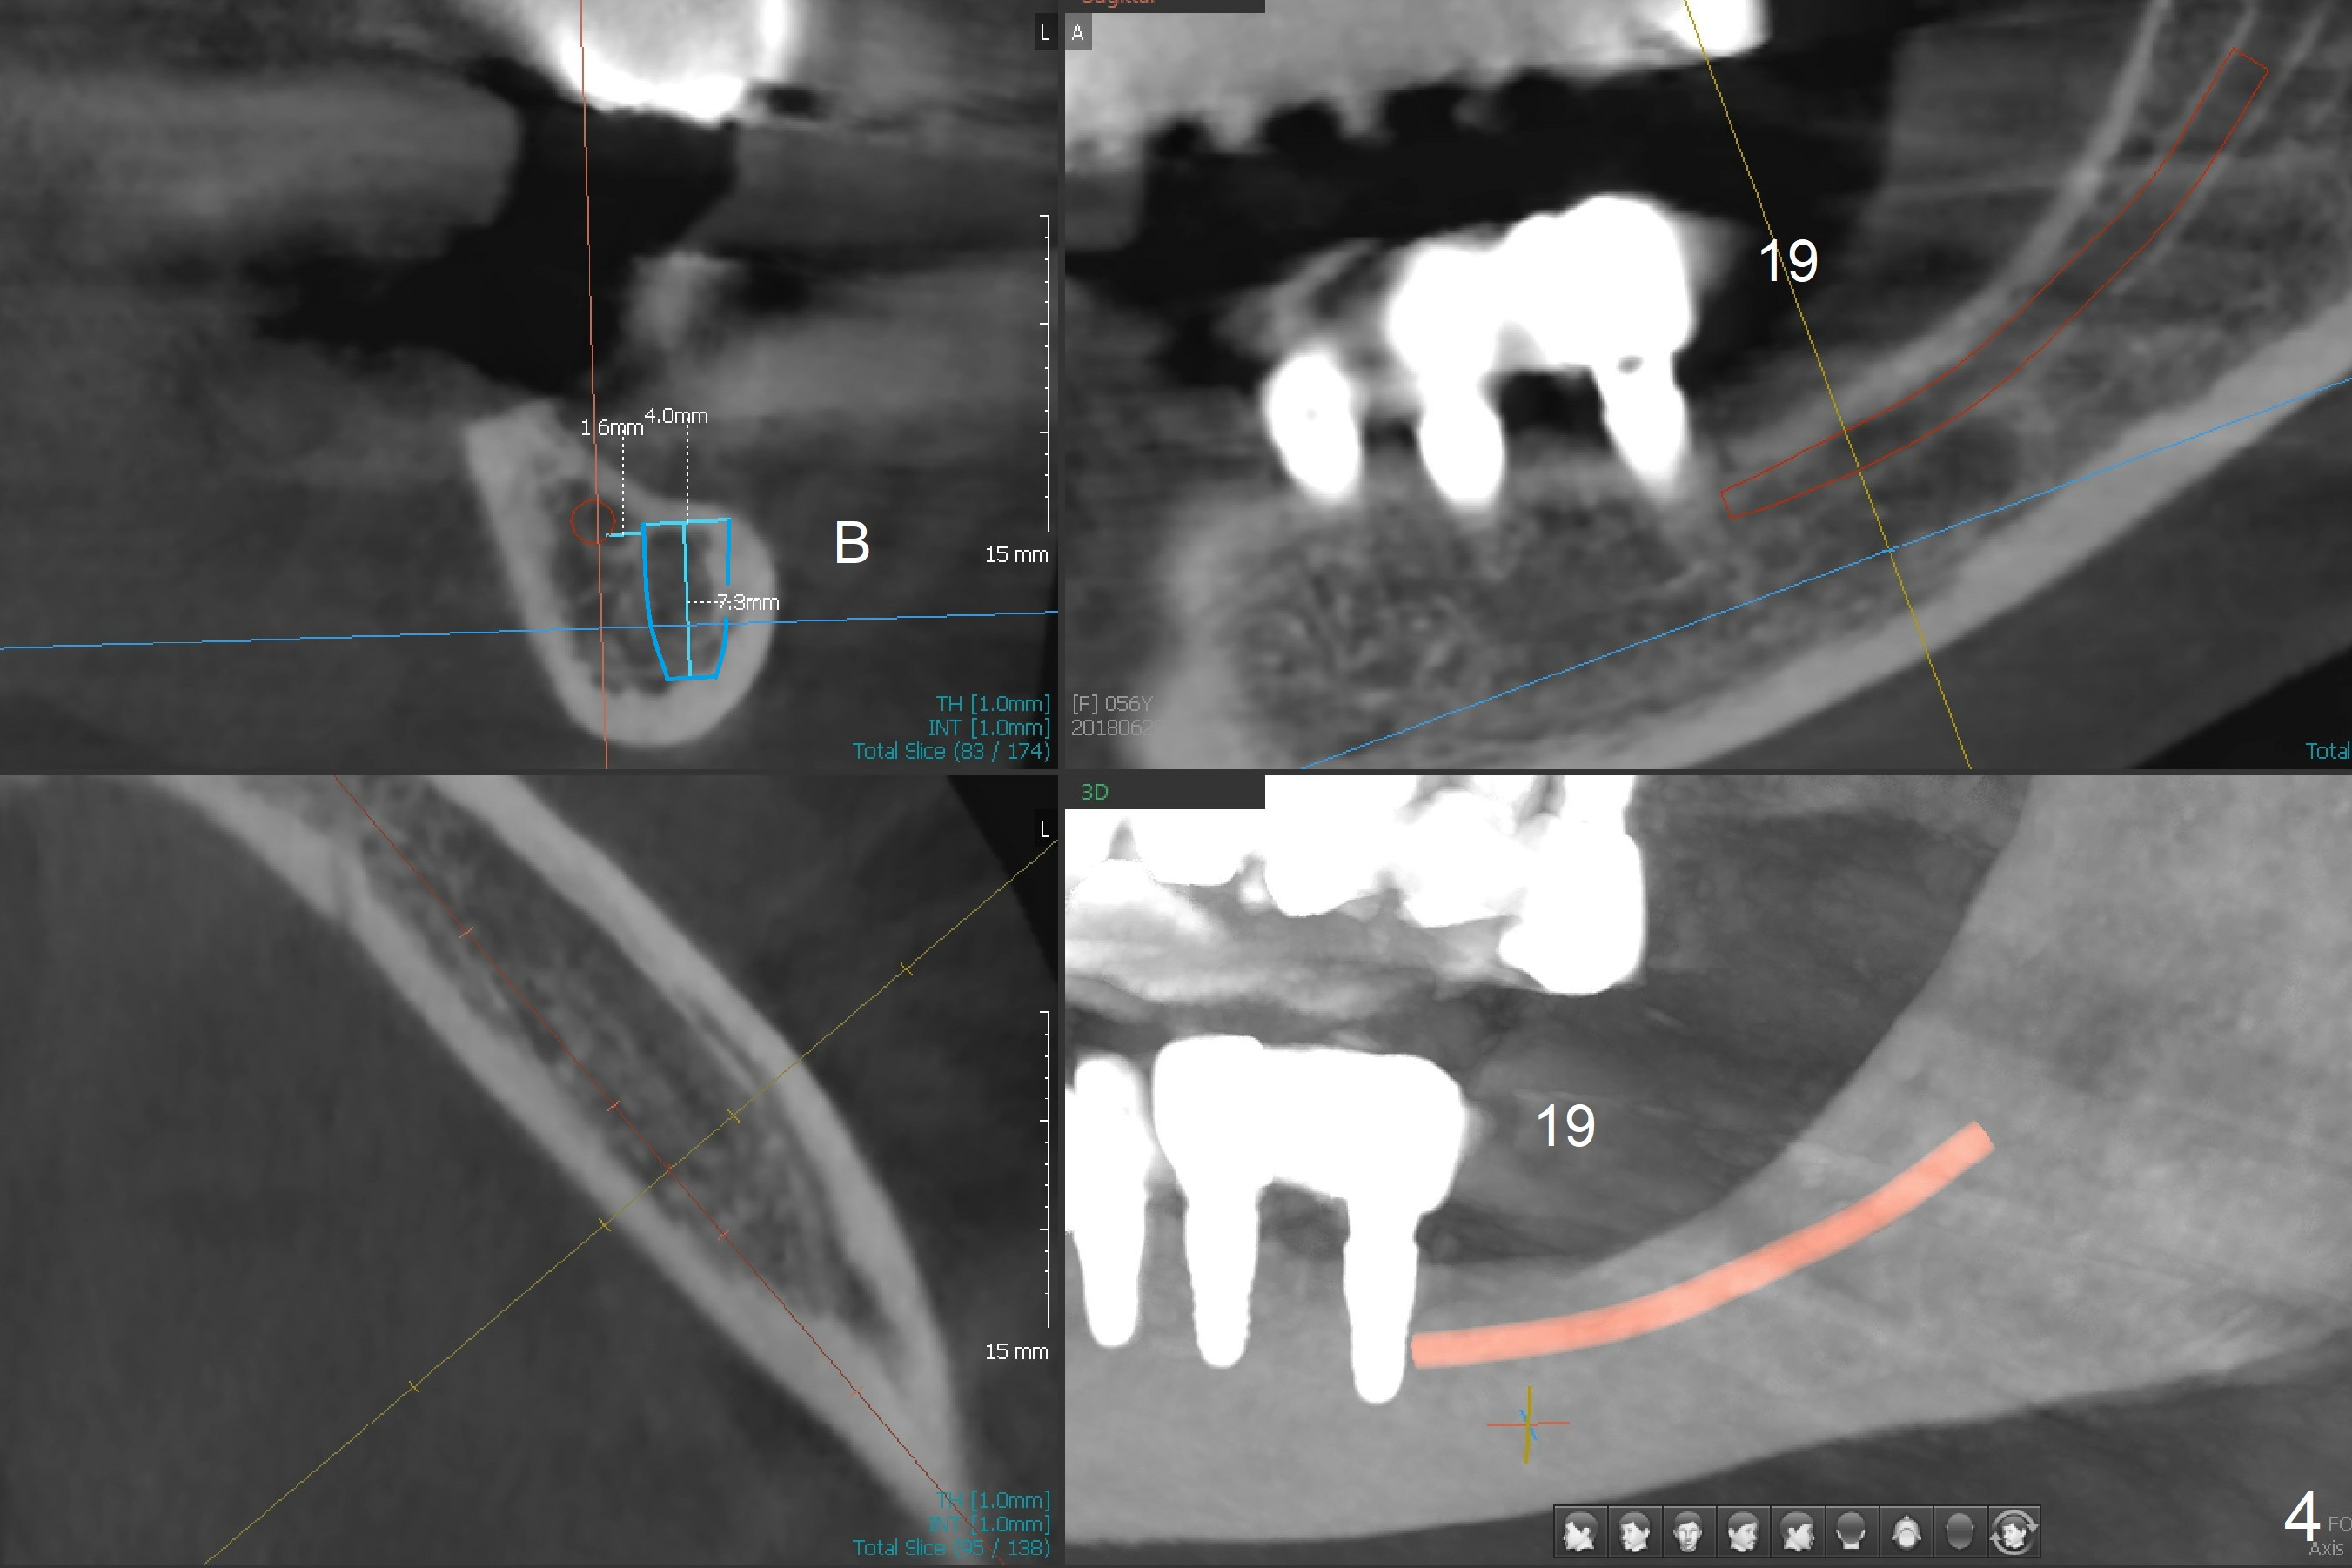

A 56-year-old woman with atrophic jaws requests redoing lower implant restoration (in function 1 year) for cosmetic reason and placing an implant at #19 (because she could not masticate on the left, Fig.1). While the 3.8x8.5 mm implants at #31 and 20 are placed lingual (L) to the Inferior Alveolar Canal (IAC, Fig.2,3) "free hand", can a 4x7.3 mm implant (Fig.4 blue outline) be placed buccally (B) at #19 with a guide?